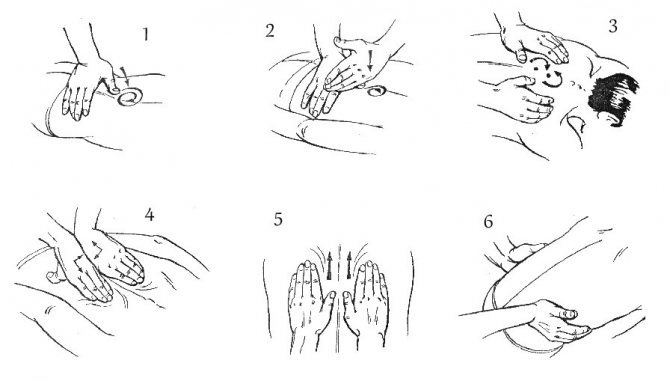

Массаж

Процедуру не делают, если заболевание находится в стадии обострения. Массаж в период ремиссии улучшает состояние больного, расслабляет мышцы. Усиленное питание тканей во время сеансов, снабжение кислородом способны укрепить мышечный корсет, вернуть прежний объем движений (хорошая трофика делает связочный аппарат более эластичным).

Лечебный массаж снимает отечность, освобождает нервные корешки. Процедура ускоряет проводимость нервных импульсов, влияет на процессы восстановления костной ткани. Доказана эффективность массажа при смещении межпозвоночного сустава. Существует несколько видов массажа, которые можно использовать при грыже: